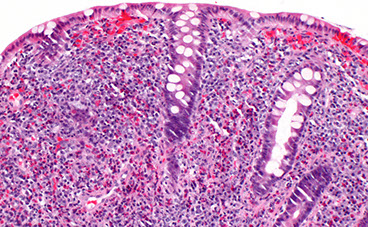

Microscopic pathology of Crohn disease. A, Haphazard crypt organization results from repeated injury and regeneration. B, Noncasearing granuloma. C, Transmural Crohn disease with submucosal and serosal granulomas (arrows)

Microscopically, Crohn disease is characterized by transmural inflammation. Here, inflammatory cells (the bluish infiltrates) extend from mucosa through submucosa and muscularis and appear as nodular infiltrates on the serosal surface adjacent to fat. Note the granulomatous inflammation.